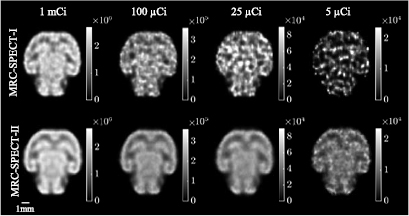

3.3. Mouse brain phantom studies

Compared to the resolution phantom used above, the brain phantom described in section 2.4 had a much broader distribution of activity, and allowed us to further evaluate the capability of MRC-SPECT-II. As shown in figure 6, we simulated a phantom filled with different activity levels ranging from 1 mCi to 5 μCi, and compared the reconstructed images at similar spatial resolution of around 0.5 mm. Given the >30 times greater sensitivity, the MRC-SPECT-II system offered greatly reduced imaging noise. With a very low activity of 5 μCi in the whole brain, the MRC-SPECT-I image became very noisy and virtually unusable, while the MRC-SPECT-II image retained reasonable quality.

Figure 6. Reconstructed images of the mouse brain phantom; the reconstructed images had similar resolution for each activity level; MRC-SPECT-II with the proposed HPWF (MRC-SPECT-II-C) was used. Resolution was evaluated in terms of LIR (equation (5)) at the center of the FOV. The filter FWHM of MRC-SPECT-II was fixed at 0.5 mm, and we varied the filter size of MRC-SPECT-I to minimize the LIR difference.